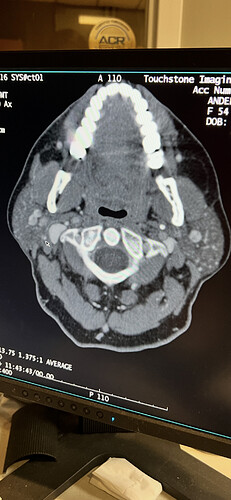

I would’ve posted pictures from my CT earlier but I cannot get the disk to work these images that I have are not great because I’m just taking a picture with my phone… I took a bunch.

@Minh2025 - I’m sorry your disc isn’t being cooperative. The pictures you shared are pretty good & do show that your left IJV is being compressed more by C1 than by your styloid.

Both your IJVs are compressed against the wings of your C1 tranverse process.Your styloids aren’t causing any compression (at least at this specific slice). C1 shave on both sides could help open the IJVs up. We’ll have to see a 3D reconstruction to see the full lengths of your stylohyoid ligaments.

Your left ICA is pushed up against your left IJV which I don’t see often. Not sure if this is contributing anything or not. I’d say stay away from atlas adjustments. Any temporary loosening or shifting of C1/C2 could cause temporary flare ups of your symptoms. Your vagus nerves may be compressed between your IJVs and C1 as well.